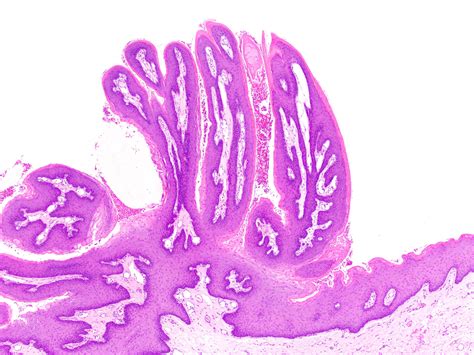

Identifying an Oral Squamous Papilloma often involves observing its distinct morphology. Clinicians look for specific visual cues that differentiate this lesion from other oral pathologies like focal epithelial hyperplasia or squamous cell carcinoma. Because they are exophytic, they grow outward from the surface, often resembling a small cluster of grapes or a delicate cauliflower head.

• Biopsy: The gold standard for diagnosis. A small sample of the tissue is removed and examined under a microscope to confirm the presence of koilocytes—cells characteristic of HPV infection.